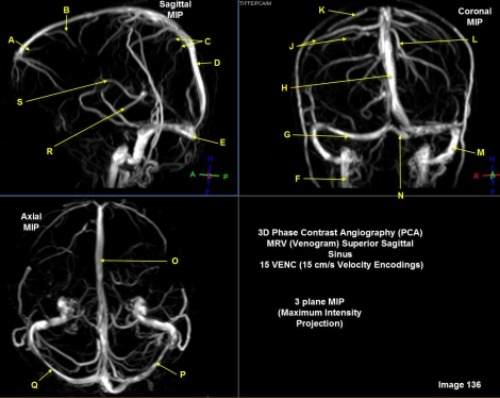

Letter R in Image 137 is pointing to:

A. Pons

B. Cerebral peduncle

C. Thalamus

D. Caudate nucleus

E. Cerebellum

F. Basal vein

Letter N in Image 137 is pointing to:

C. Genu of corpus callosum

D. Body of corpus callosum

E. Splenium of corpus callosum

Letter J in Image 137 is pointing to:

A. Aqueduct of Sylvius

B. Third ventricle

C. Sulcus

D. Fourth ventricle

E. Superior sagittal sinus

F. Lateral ventricle

Letter H in Image 137 is pointing to:

A. Grey matter

B. White matter

Letter O in Image 137 is pointing to:

Letter M in Image 137 is pointing to:

Letter X in Image 137 is pointing to:

A. Anterior frontal vein

D. Vein of galen

Letter B in Image 137 is pointing to:

Letter S in Image 137 is pointing to:

A. Optic chiasm

B. Pituitary gland

C. Inferior colliculus of midbrain

D. Internal carotid artery

E. Vein of galen

F. Straight sinus